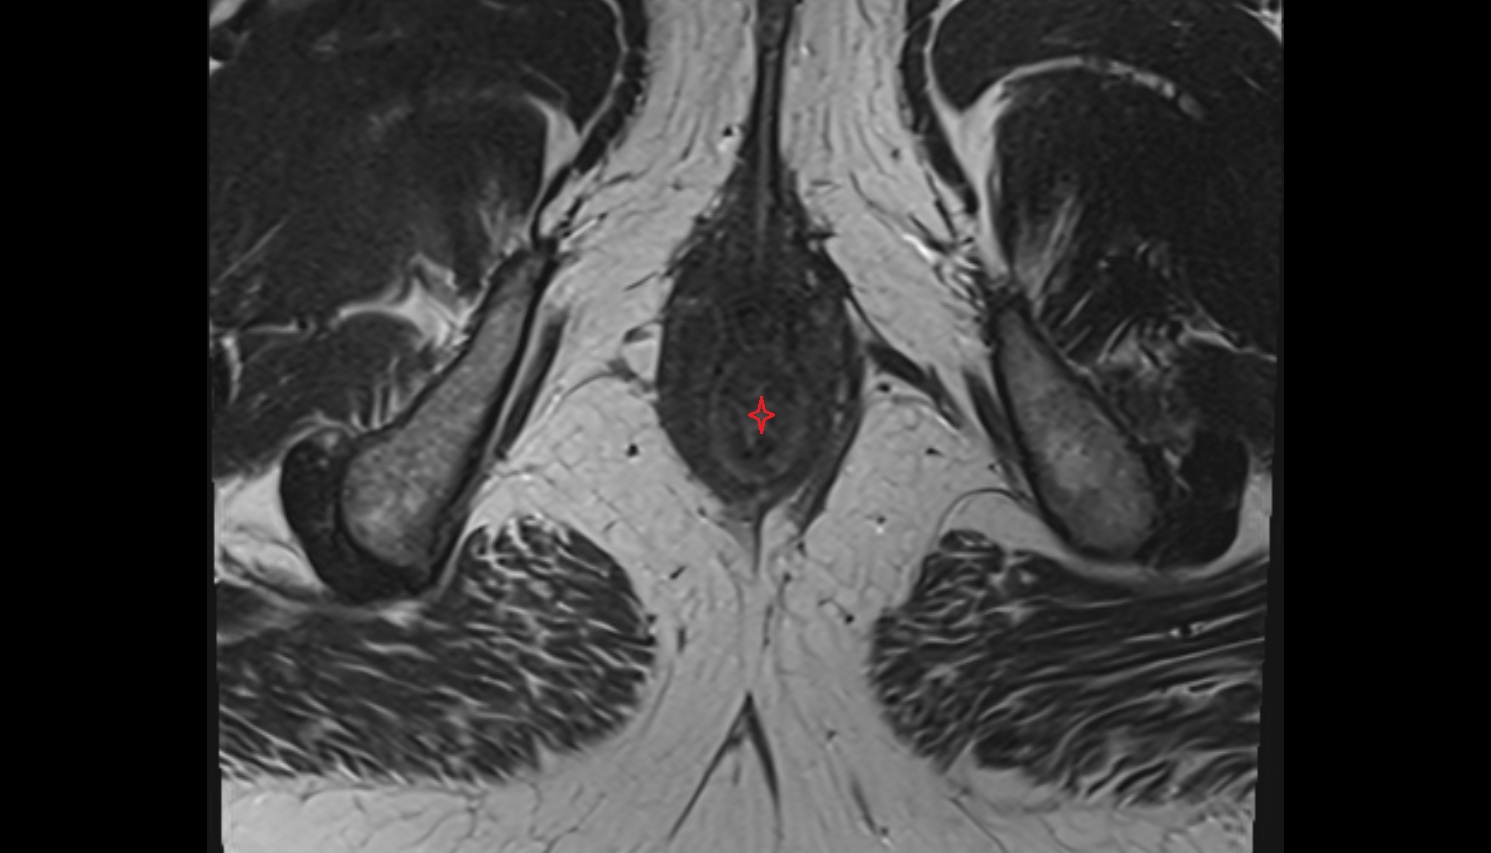

- Peripheral zone of prostate

- Anterior Fibromuscular Stroma of prostate

- Central zone of prostate

- Transitional zone of prostate